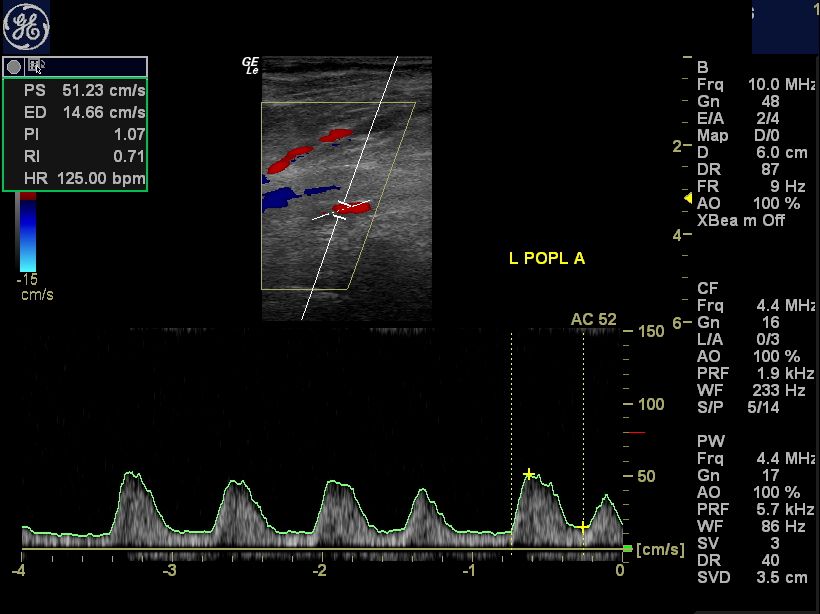

Color and pulsedwave Doppler sonograms of normal lower extremity arteries with parameters. Top Doppler Pulses Foot Resting abi testing should be performed for patients with history or. Learn how to palpate and describe the four pulses in the legs, including the dorsalis pedis pulse over the foot arch. Patients on a backboard or in a lower extremity splint should have their pedal pulse checked as part of their continuous assessment. Master how to interpret both audible. Doppler Pulses Foot.